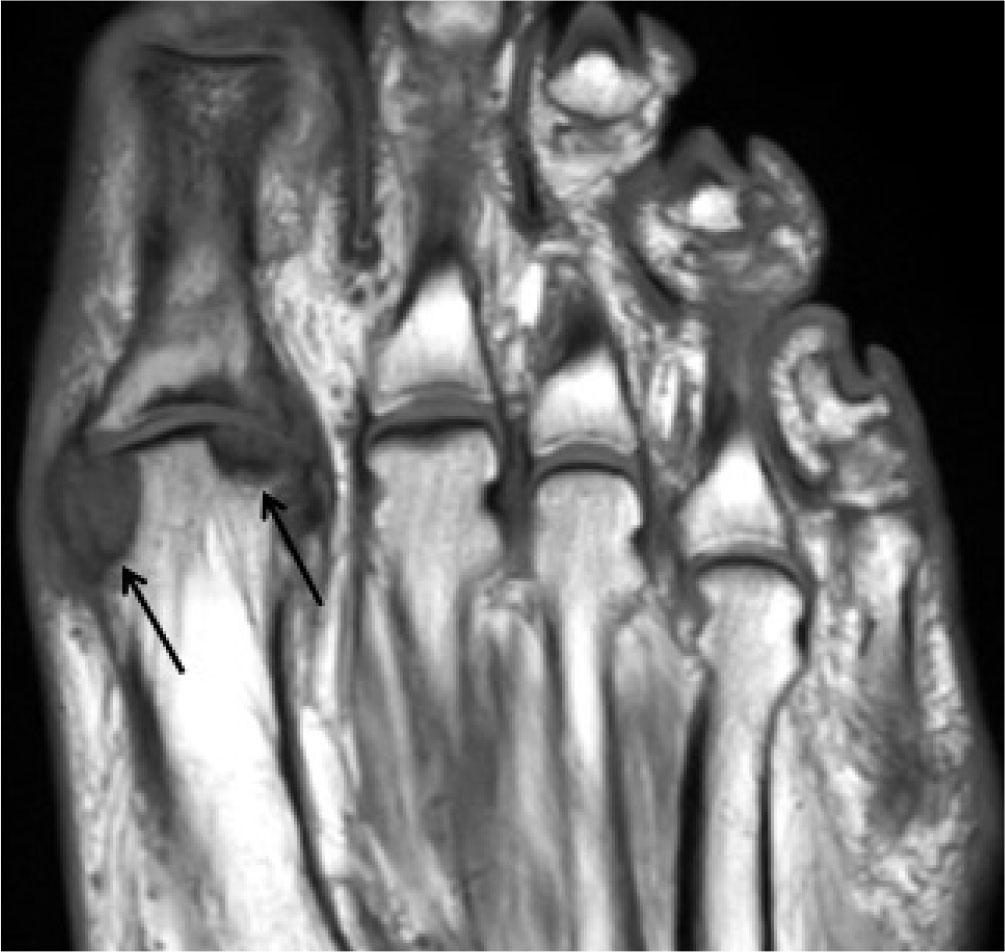

Fig. 28.

Gout: Coronal T1-W MR image of the foot shows large hypointense erosions in the head of the 1st metatarsal (black arrows) with adjacent hypointense tophi. There is also a large hypointense tophus over the base of the 5th metatarsal (white arrow). Note the characteristic clearly demarcated erosion